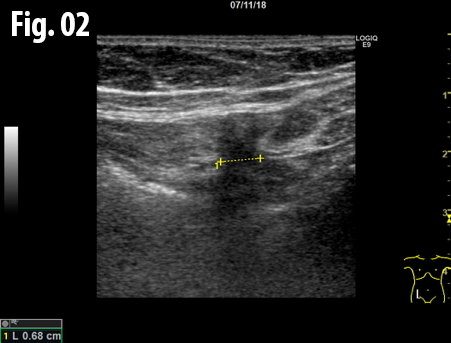

An ultrasound examination of the abdomen was performed using a GE Logiq E9 system with a linear array transducer and centre frequency of 9 MHz. The patient was examined in the supine and standing position including the Valsalva manoeuvre. The examination revealed an incarcerated hernia between the rectus abdominis and transversus abdominis muscles at the level of the anterior superior iliac spine. The dimension of hernial orifice was 1.3 x 0.7 cm and contained preperitoneal fat without any bowel loops. There was no change in size or content of the hernia on standing or Valsalva, and no signs of strangulation.

Figure 1: The hernia containing preperitoneal fat, axial view obtained with the patient standing. The marker indicates the hernia, the blue arrow the transversus abdominis muscle and the gray arrow indicates the rectus abdominis muscle.